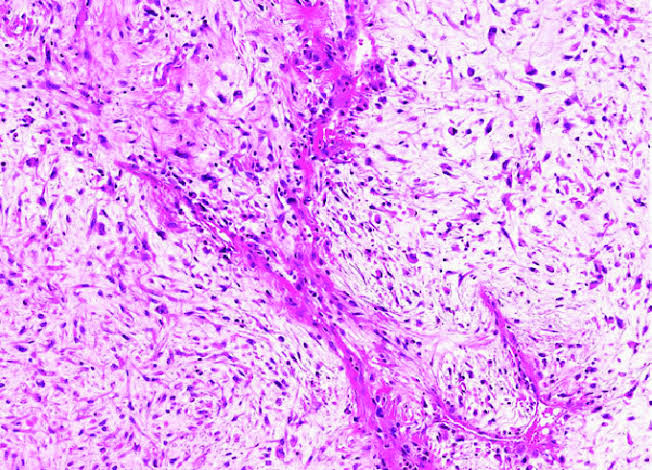

@MirunaPopescu13

❓ Let’s do a quick #BSTPath quiz ❓ 60 y/o F with a retroperitoneal mass 🔪 Follow the 🧵 👇🏽 for the answers & for a short tweetorial (1/11) #PathTwitter #pathoutpic #pathtweetorial